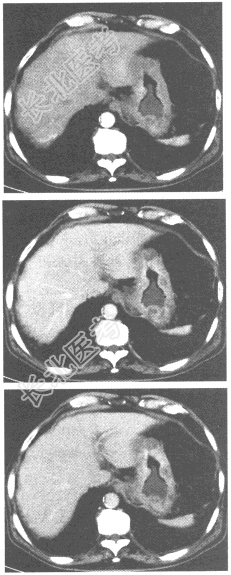

- [材料题] 患者,男性,79岁,上腹部疼痛,不易缓解,吐咖啡色血液。行上腹部CT增强扫描,如下图。

- 简答题1、请问该患者应首先考虑的诊断是什么?

- 简答题2、请描述一下该病的转移方式。

- 简答题3、请问该病的治疗方案有哪些?